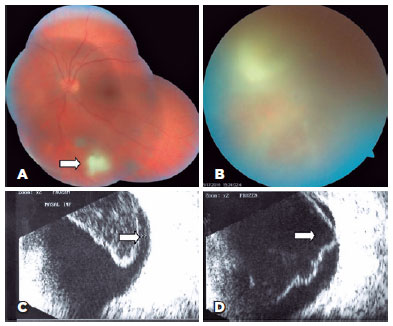

Retinochoroidal lesions were mainly located in the superotemporal (14 eyes, 29.8%) and inferonasal (11 eyes, 23.4%) quadrants. Eighteen (38.3%) and 29 eyes (61.7%) had a lesion size ≤2 DD, respectively. Furthermore, satellite lesions (Figure 1A) associated with a pre-existing retinochoroidal scar and isolated lesions were present in 37 (78.7%) and 10 eyes (21.3%), respectively. Three patients (6.4%) achieved a positive IgM result in a serologic analysis, indicating the acquired form of the disease.

13-fig01.jpg)

The ultrasonographic characteristics observed in our patients are presented in table 1. Vitritis (Figure 1B), which appeared as a punctate vitreous echo on ultrasonography, was detected in all 47 eyes (100%) and was either diffuse (40 eyes, 85.1%) or localized (7 eyes, 14.9%). PVD (Figure 1C) was identified in 36 eyes (76.6%) and was either partial (12 eyes, 25.5%) or total (23 eyes, 48.9%). No sign of PVD was noted in 11 eyes (23.4%). Of the 36 eyes with PVD, 35 (97.2%) exhibited hyaloid thickening, and 4 (11.1%) exhibited adherence to the exudative lesion (Figure 1D). Vitreoschisis (Figure 2A) and chorioretinal thickening (Figure 2B) were each identified in 12 eyes (25.5%), while perilesional non-rhegmatogenous retinal detachment (Figure 2C) was observed in 5 eyes (10.6%). A comparison of information from the questionnaire with the ultrasonography findings revealed that the latter could accurately demonstrate the location of the exudative focus in 12 eyes (25.5%).